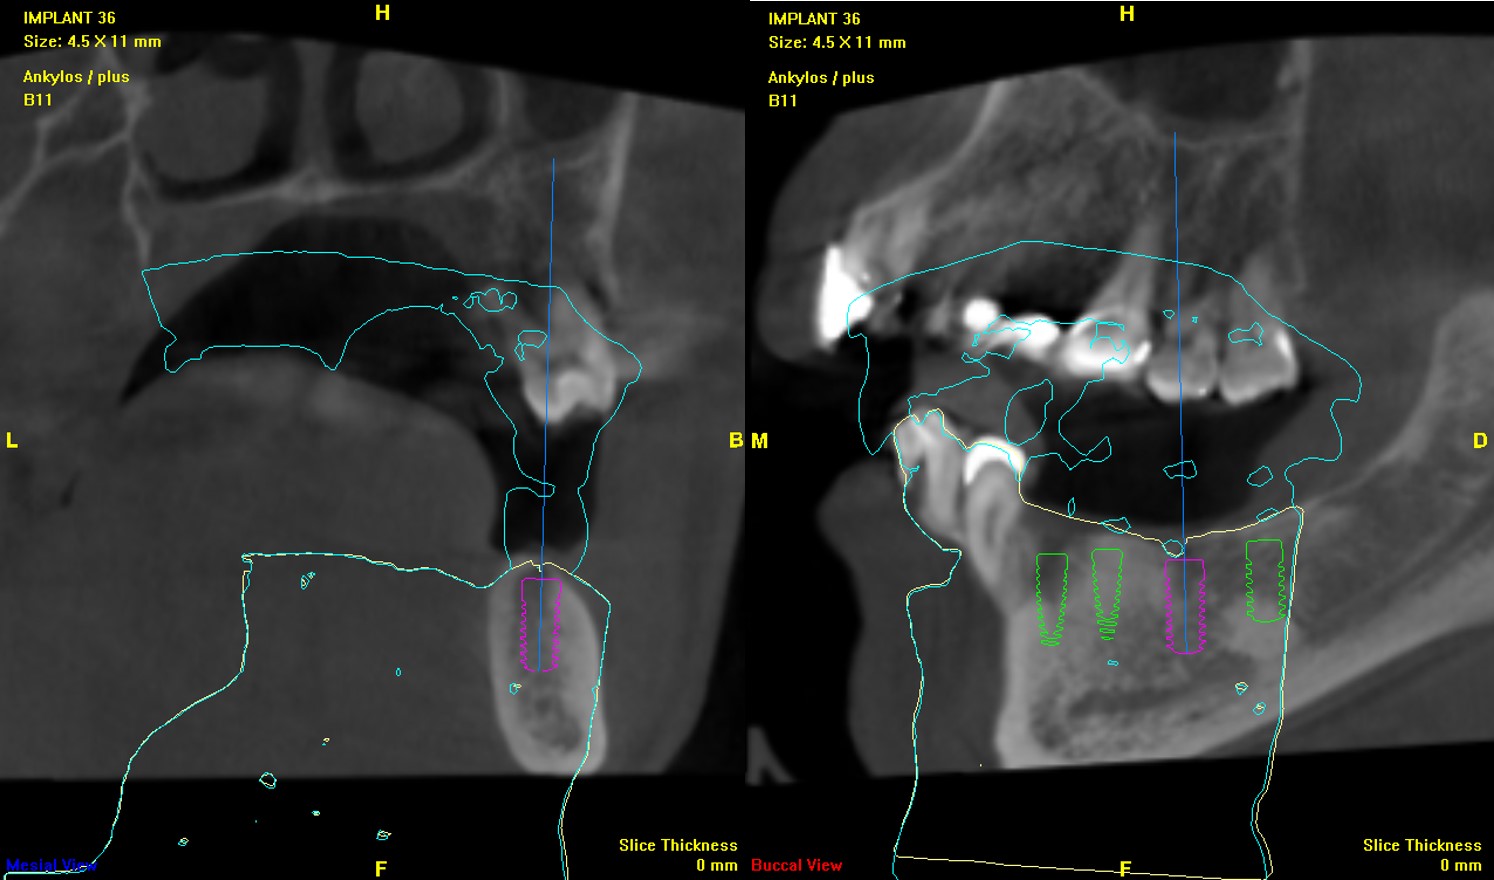

植體植入與補骨手術:#34-37

▼檢查及分析完成後,醫生就開始了植體植入與補骨手術